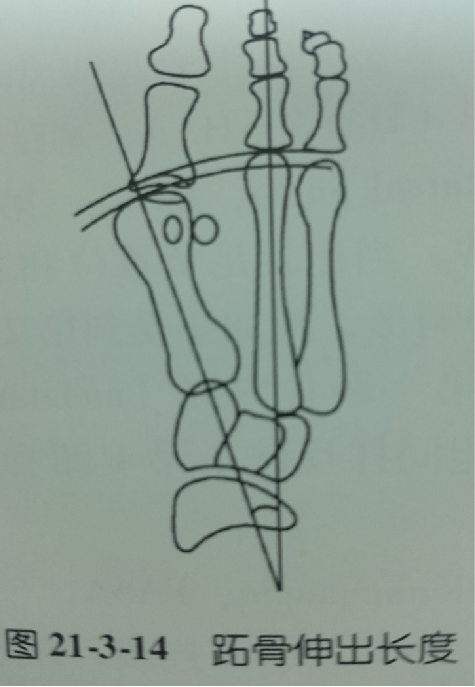

跖骨伸出长度(MPD)  以第1、2跖骨轴线交点为圆心分别向第1、2跖骨远端关节面画弧,两弧之间距为第1、2跖骨相对长度